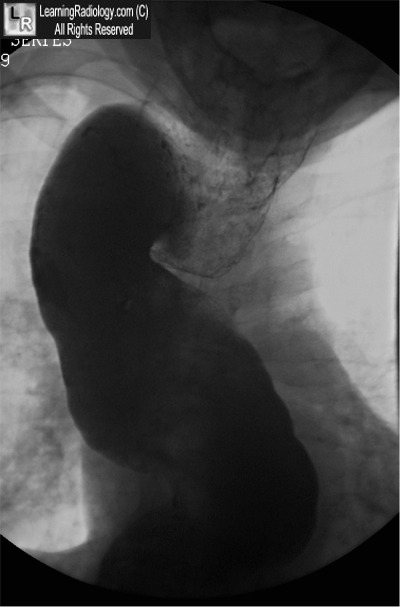

Additional Image-Esophagram

Esophagram

5. Achalasia